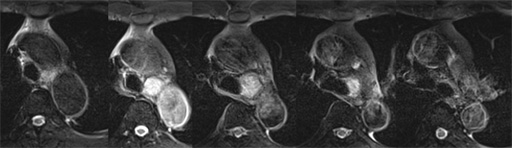

症例7 : 図11 MRI fat sat T1WI (dynamic study)